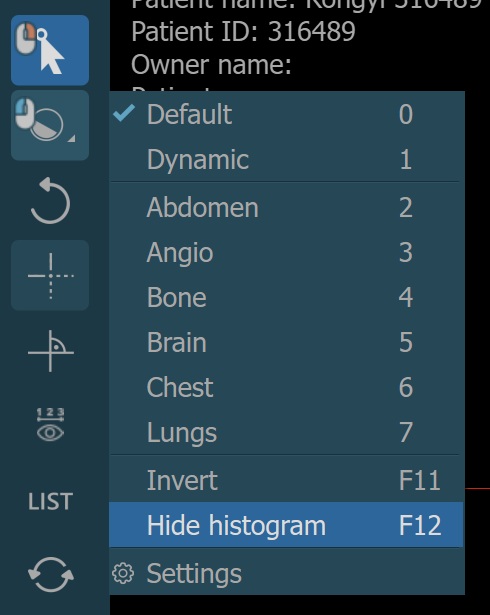

Additionally, choose one of the available windowing presets from the dropdown to directly apply the corresponding window center and window width values.

The windowing presets are also available from the windowing menu when the default windowing mode is active.